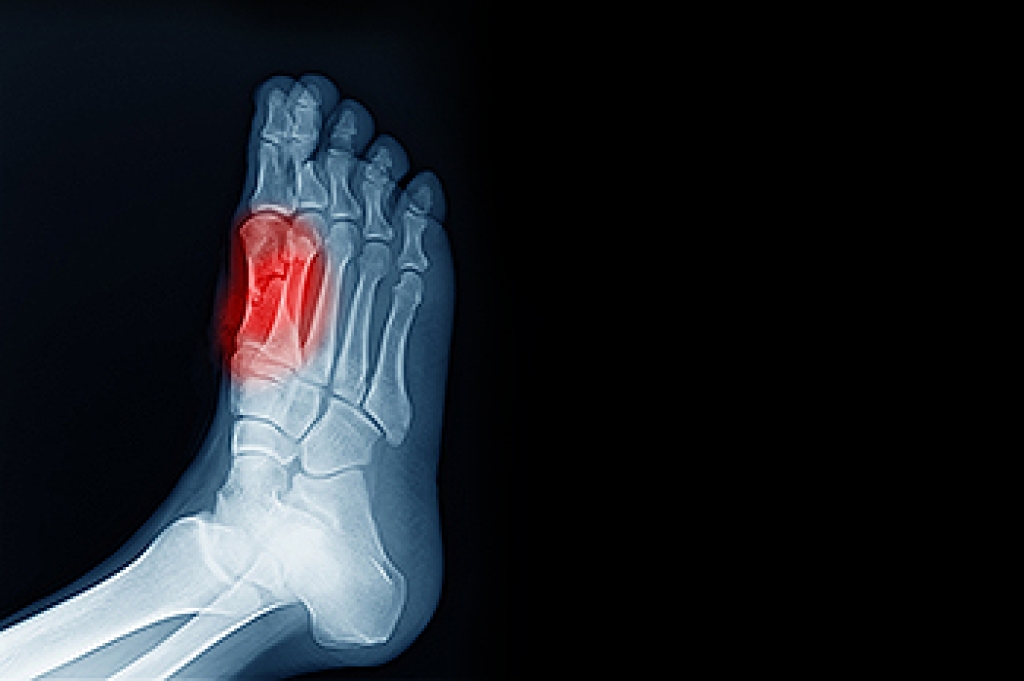

Poor blood circulation in the feet and legs is can be caused by peripheral artery disease (PAD), which is the result of a buildup of plaque in the arteries.

Plaque buildup or atherosclerosis results from excess calcium and cholesterol in the bloodstream. This can restrict the amount of blood which can flow through the arteries. Poor blood circulation in the feet and legs are sometimes caused by inflammation in the blood vessels, known as vasculitis.